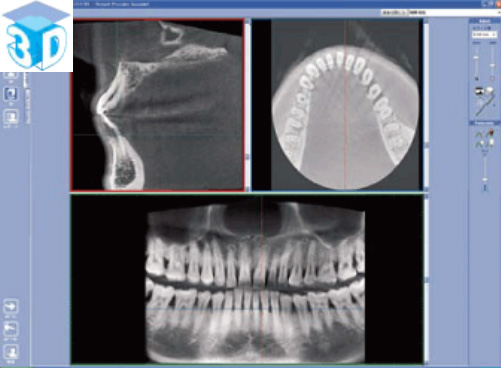

上図のような歯科用CTから得られる三次元的情報は、インプラント治療、歯周病治療、根管治療親知らずの抜歯など歯科治療のあらゆる分野での診断に必要不可欠なものとなってきています。詳しくはGCホームページをご覧ください。